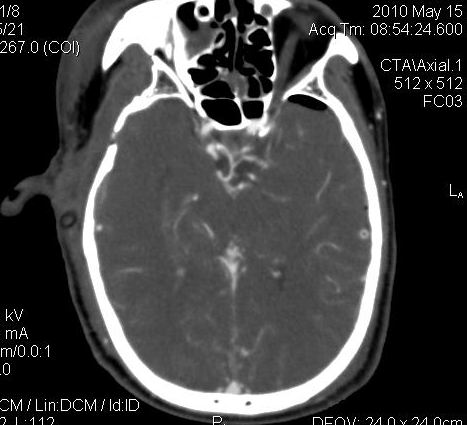

男.60岁,渐进性意识不清,ct检查双侧额颞顶部硬膜下血肿,开颅术后行脑血管cta,大脑中动脉起始部见一瘤状血管扩张。请各位老师留下宝贵意见

太常见了,报动脉瘤就可以

符合动脉瘤表现。

符合动脉瘤表现。

动脉瘤。

颅内动脉瘤。

后重建做得不是很好看,要将维蒂斯环充分显示,最好在增加一个mip。这样不好定位。

小动脉瘤

典型

符合动脉瘤的表现

动脉瘤

符合动脉瘤表现。

小动脉瘤

典型